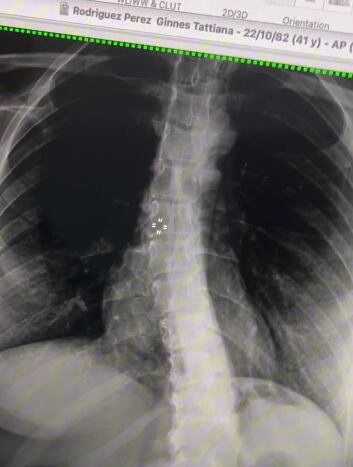

“Esta es mi columna y necesito operarla. Debido a todo lo que atravesamos con Gerardo (su esposo), lo pospuse, pero lo retomé a finales del 2023″, expresó la comunicadora.

La escoliosis es una condición médica en la que la columna vertebral se curva de manera anormal hacia un lado, formando una especie de “S” o “C” en lugar de la línea recta normal. Esta curvatura puede ser leve o severa y puede afectar tanto a niños como a adultos.